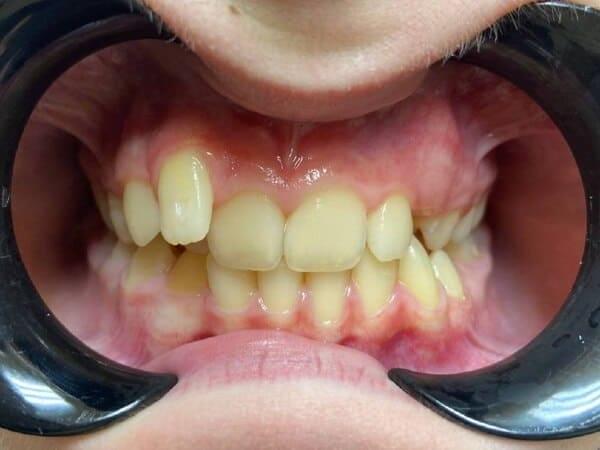

Підлітковий вік — це вирішальний час для остаточного формування прикусу та естетики обличчя. Це ідеальний період для ортодонтичних маніпуляцій, адже саме зараз можна досягти максимального результату з мінімальними зусиллями.

Кісткова тканина в підлітковому віці ще є податливою, що дозволяє досягти чудових результатів значно швидше та з меншим дискомфортом, ніж у дорослих. Нерідко результати, досягнуті в цьому віці, неможливо отримати в дорослому без складних хірургічних втручань.

Наш ортодонт спеціалізується на роботі з підлітками та володіє різними техніками та інструментами для корекції прикусу:

ми використовуємо різні види брекетів — металеві, керамічні, самолігуючі. Це дозволяє індивідуально підібрати систему, яка буде найефективнішою та найкомфортнішою для вашої дитини.

для тих, хто шукає більш естетичне та комфортне рішення, ми пропонуємо лікування за допомогою прозорих елайнерів. Вони дозволяють гармонізувати прикус, залишаючись майже непомітними.